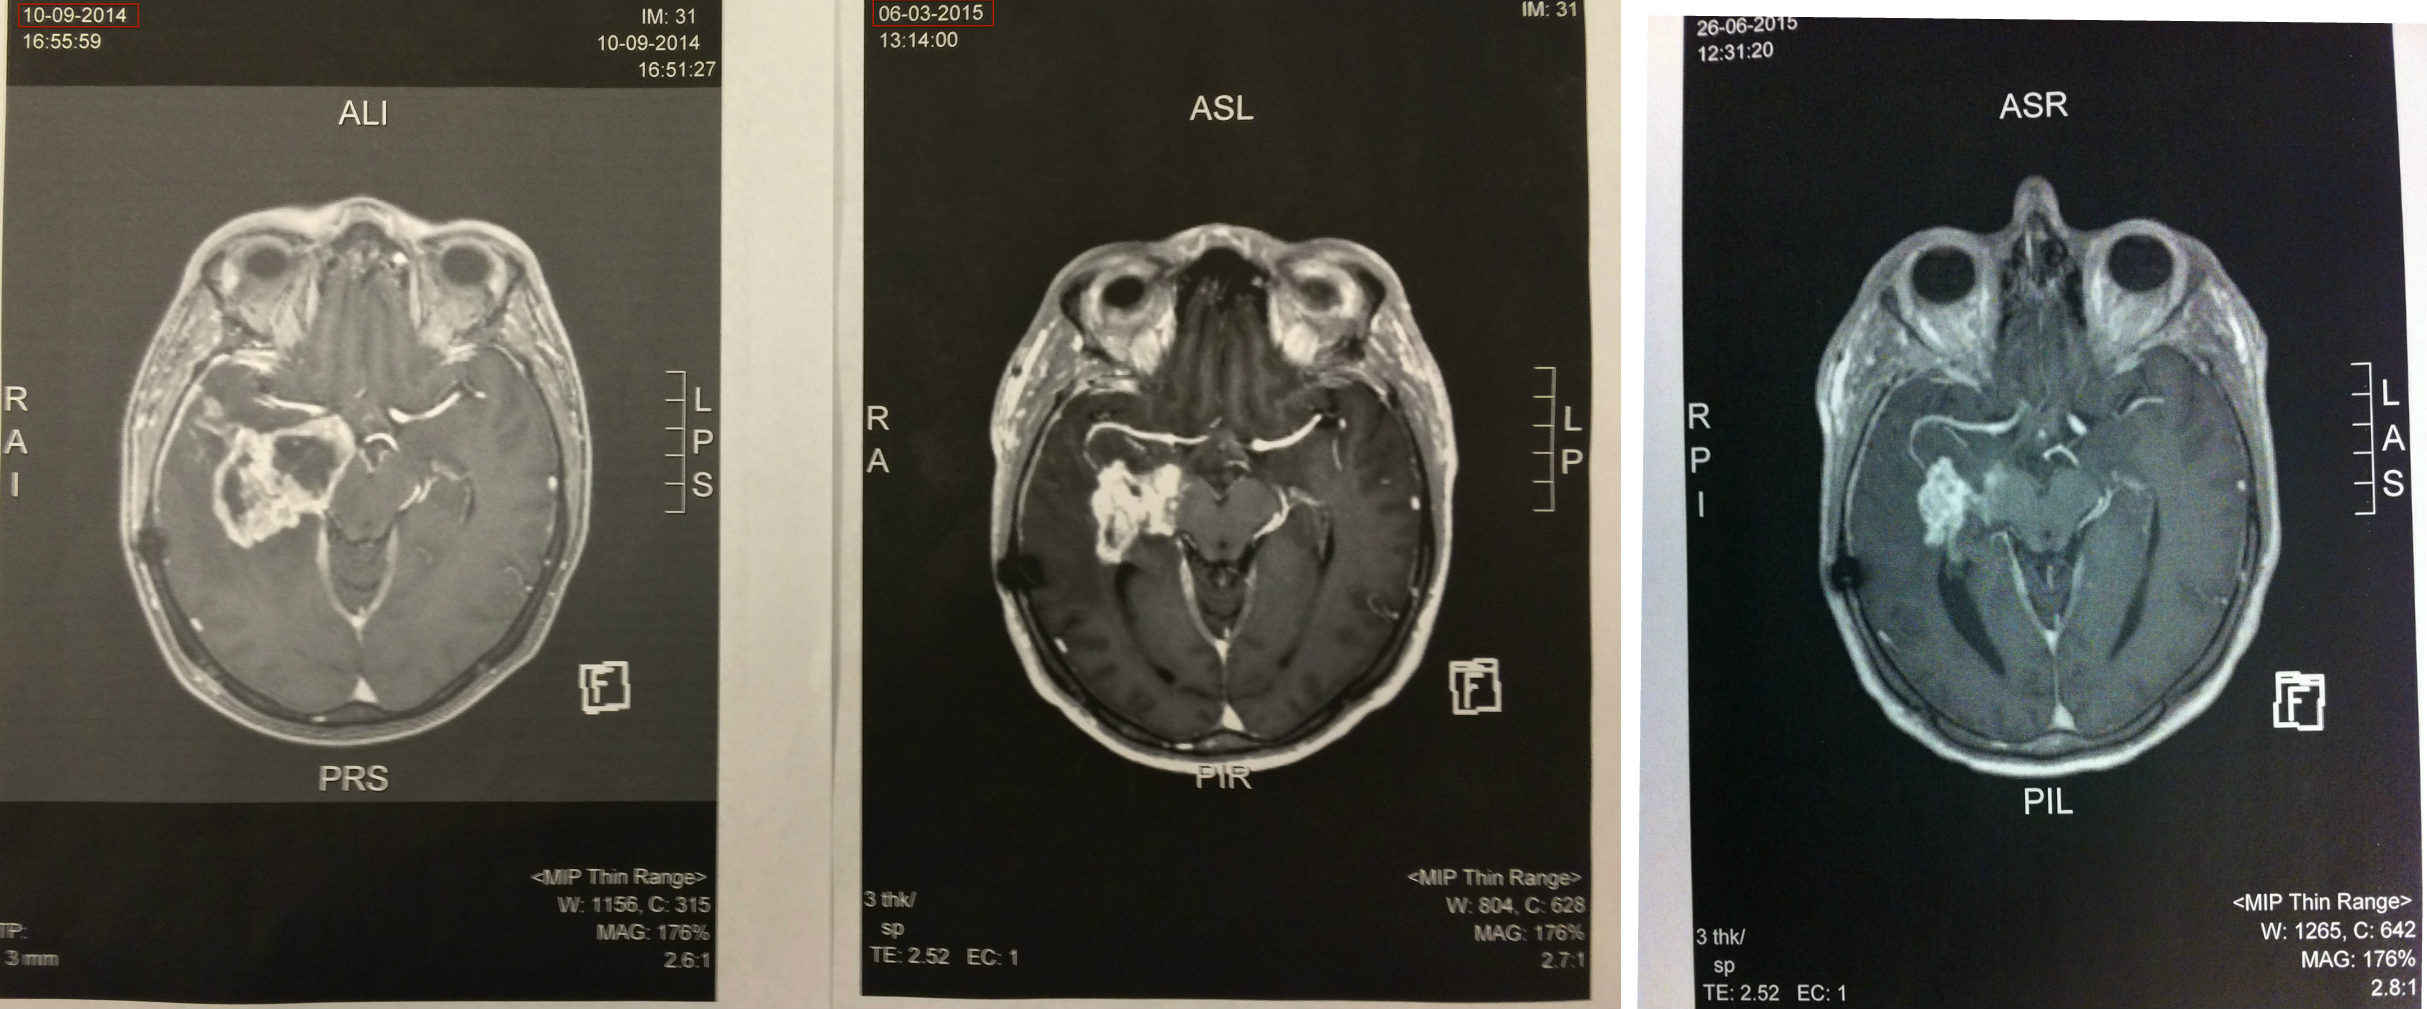

12+ Grade 4 Brain Tumor Treatment PNG. Primary brain tumors among adults are astrocytoma, meningioma, and oligodendroglioma. Treatment for a brain tumour aims to remove as much of it as possible and try to stop it coming back.

There may be areas of dead cells. According to the world health organization (who) classifications of brain tumors, astrocytomas range from grade 1 (most benign) to grade 4 (most malignant). The brain tumor grading system features four distinct grades and provides your care team with an understanding of how the tumor grows. Steroids are often used to reduce the buildup of fluids around a tumor (edema) surgery: